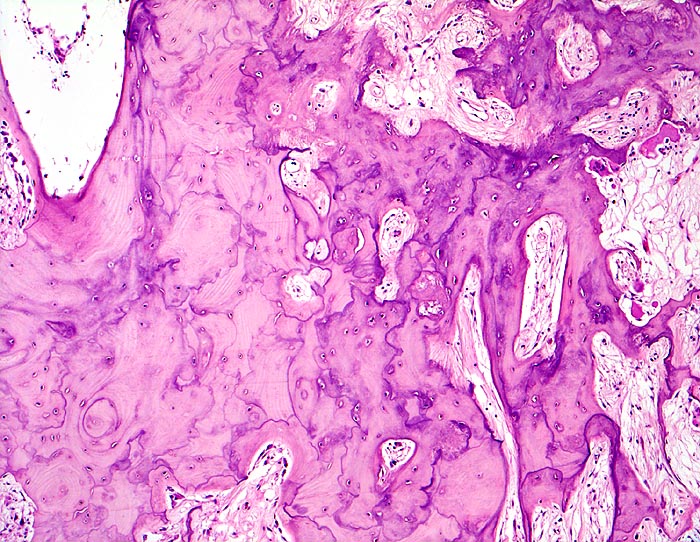

An den betroffenen Stellen ist sowohl der Knochenabbau als auch der Knochenanbau gesteigert. Die Osteoklasten sind auffallend gross und enthalten sehr viele Kerne (> 3518). Die aktivierten Osteoblasten produzieren verdickte und grob geflochtene Spongiosabälkchen. Der neugebildete Knochen ist strukturell und morphologisch abnorm und schlecht mineralisiert. Der Knochen wird dadurch weich und anfällig auf Frakturen oder Deformation unter Belastung (nach vorne gebogene Säbelscheidentibia). Das Knochenmark wird ersetzt durch fibrovaskuläres lockeres Stroma, welches an Granulationsgewebe erinnert. Mikroskopisch werden eine osteolytische Initialphase, eine Umbauphase mit verstärkter Knochenneubildung und eine sklerosierende Stabilisationsphase mit strukturellem Umbau und Spongiosierung der Kortikalis (verbreiterte spongiosaartige Kortikalis) unterschieden.

• Die Spongiosabälkchen sind auffallend verdickt, vermehrt und unregelmässig geformt.

• Prominente Zementlinien sind mosaikartig angeordnet.

• Riesenosteoklasten mit über 20 Kernen sind an der Knochenoberfläche erkennbar.

• Vermehrte kubische aktive Osteoblasten bauen Knochen an.

• Lockere Markfibrose.